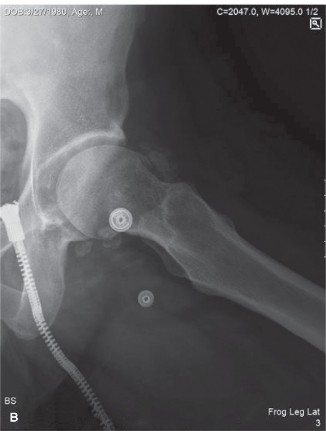

Plain Radiography Findings

Initial radiographs of the right knee, including anteroposterior, lateral, skyline, and weight-bearing views, demonstrated multiple, well-circumscribed, oval or curvilinear radiopacities within the joint space, varying in size from a few millimeters to approximately 1.5 cm. These calcified loose bodies were most concentrated in the suprapatellar pouch, the medial and lateral gutters, and the posterior recesses of the knee.

The radiographic pattern exhibited the classic "ring-and-arc" chondroid mineralization, pathognomonic for hyaline cartilage matrices that have undergone endochondral ossification. Importantly, the underlying joint space was relatively preserved, with minimal osteophyte formation or subchondral sclerosis. This lack of advanced degenerative joint disease is a critical radiographic differentiator, suggesting that the loose bodies are the primary pathology (Primary Synovial Chondromatosis) rather than secondary osteochondral fragments resulting from advanced osteoarthritis or neuropathic arthropathy. Extrinsic scalloping of the anterior femoral cortex was noted, a secondary sign of chronic pressure erosion from the hyperplastic synovial masses.